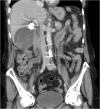

Presentation of case: A 76-year old female underwent laparoscopic cholecystectomy because of a severe acute on chronic cholecystitis. A massive arterial bleeding occurred during surgery, which was controlled with hemoclips. Approximately one week after surgery the patient developed severe colic pains and cholestatic liver enzyme alterations. Endo-ultrasound showed normal-width bile ducts, however during a subsequent ERCP haemobilia was observed. On computed tomography a pseudoaneurysm of the right hepatic artery was seen. Selective embolization was initially successful, however, a rebleed was observed two weeks later and a 6 × 50 mm Viabahn stent graft was placed in the right hepatic artery uneventfully. The patient remained free of complaints during 3-years of follow-up.